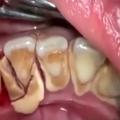

zobni kamen

ogled na lastno odg…

Po ogledu tega videa si boste želeli takoj umiti zobe

Koliko časa ponavadi posvetite ustni higieni? Po ogledu tega videa boste ta čas zagotovo podvojili … Ogled osebam z obč…